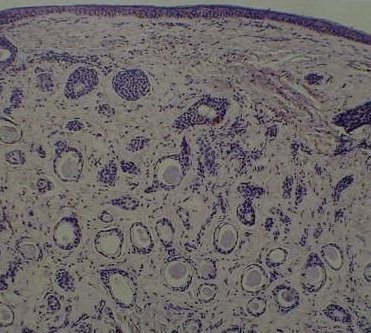

This teenager presented with a nodular lesion below the left eye. The lesion is hard to palpation. The histology is shown on the left.

Brow

Pilomatrixoma.  Brow area is a common site for this lesion.

The differential diagnosis include epidermoid and dermoid

cyst. In long-standing cases, calcification may be seen.

Magnified

Magnified view of pilomatrixoma. B represents the basophilic cells. S the shadow

(ghost) cells. Note the central clear areas. C areas of calcification.